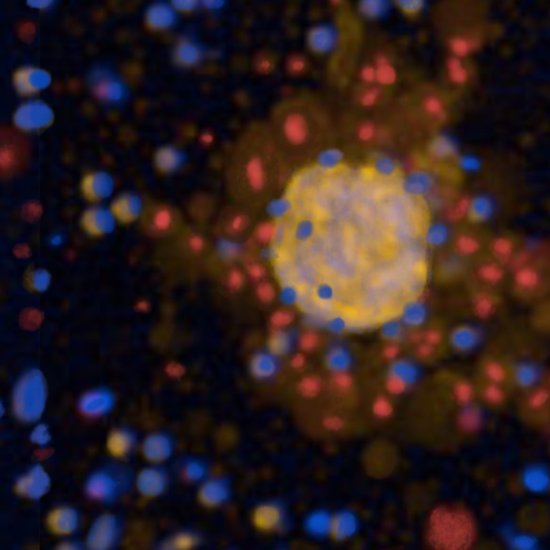

News • Tumorioide als Testobjekte

Forscher haben ein Verfahren entwickelt, mit dem sie Therapieansätze gegen Lungenkrebs an Mini-Tumoren aus Patientengewebe testen können. Das kann Ärzten bei der Behandlungsentscheidung helfen. |